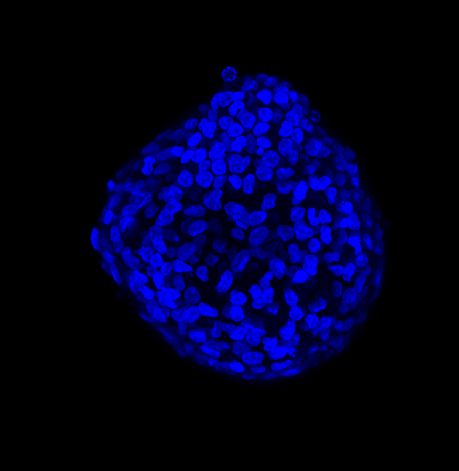

图 A:使用 20 倍空气物镜(顶部)和 25 倍硅油物镜(底部)获得的肿瘤球体 Z 堆栈的最大密度投影 (MIP)。活细胞用钙黄绿素(绿色)标记,死细胞用 PI(红色)标记。细胞核用 Hoechst(蓝色)染色。比例尺:100 um。这些图像是使用 CrestOptics X-Light V3 转盘获取的。

图 B:使用 20 倍空气物镜(左)和 25 倍硅胶物镜(右)获得的 3D 球体同一区域的放大。活细胞用钙黄绿素(绿色)标记,死细胞用 PI(红色)标记。细胞核用 Hoechst(蓝色)染色。这些图像是使用 CrestOptics X-Light V3 转盘获取的。

图 C:使用 20 倍空气物镜(左)和 25 倍硅油物镜(右)获得的球体的 3D 体积视图。活细胞用钙黄绿素(绿色)标记,死细胞用 PI(红色)标记。细胞核用 Hoechst(蓝色)染色。沿 Z 轴的比例尺:120 um。这些图像是使用 CrestOptics X-Light V3 转盘获取的。